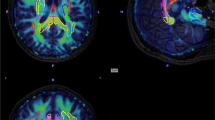

The voxel-wise comparison of the CBF maps between AFP and HI revealed a statistically significant (pFWE < 0.05) hypoperfusion in sensory-motor areas, specifically pre- and postcentral gyri (Fig. 5).

The hypoperfusion found in pre- and postcentral gyri may be interpreted in different ways; more expert players (the ones with a longer career) may have motor neural circuits more trained and more efficacious and consequently with a reduced energy consumption that requires a lower grade of perfusion. Alternatively, we may hypothesize that the summation of recurrent mild trauma is able to induce a slow but progressive neuronal density decrease [2] and consequently, a reduction in energy consumption that in turn may be supported by a lower cerebral perfusion.

Previous studies found that global cerebral perfusion is reduced in sport-associated TBI and especially in the following areas: cingulate cortex, left inferior frontal cortex, thalamus, middle and upper frontal cortex, left pre-central and post-central cortex, left transverse temporal cortex, precuneus, anterior cingulate and cerebellum [4, 6]. Moreover, brain hypoperfusion is implicated in the evolution of damage consequent to TBI, especially associated with edema, contusions and bleeding. This evidence would allow to attribute to MRI ASL technique a predictive and prognostic role of the posttraumatic functional outcome as well as to better define the severity of the TBI itself [37].